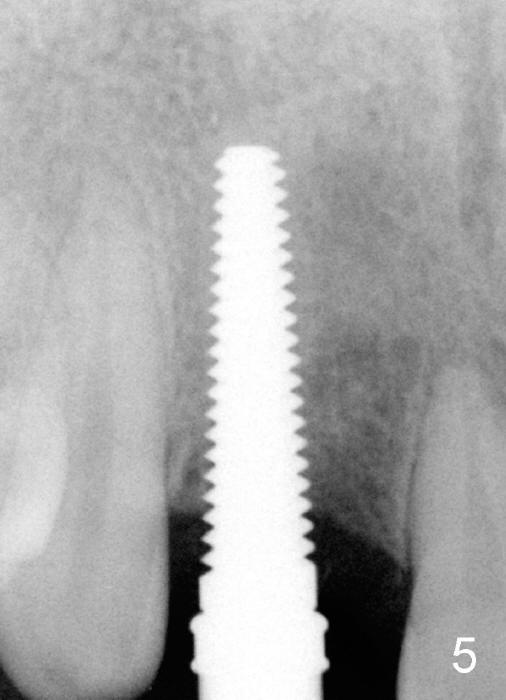

Malpositioned implant in the anterior region is cosmetically unacceptable. Immediate provisional allows us to note the issue immediately. The crown looks too long. Secondly, the provisional is easily dislodged, since the buccal aspect of the angled abutment is over trimmed (Fig.1). The implant (3.8x14 mm), which has been placed 3.5 months, is unexpectedly easily removed by reverse torque (Fig.2). The buccal wall is intact, whereas there seems to be enough bone lingually to place an implant. A small incision is made (Fig.11) so that the gingival tissue can be transferred buccally (Fig.12) and the immediate implant is to be placed palatally (Fig.13 white circle). There is no difficulty forming osteotomy in the palatal wall, followed by inserting 4.5x20 mm tap at the depth of 17 mm (Fig.3,5). But the tap is not palatal enough (Fig.4). By removing more palatal bone, the 4.5x17 implant (Fig.6) appears to be placed palatally enough for restoration (Fig.7; A: abutment; *: buccal gap). The biggest problem is that the palatal flap (Fig.7 arrowheads) cannot be pushed buccally; instead remains palatally. This leads to buccal tissue deficiency (Fig.8). Connective tissue graft is offered, but declined. The patient insists that she has low smile line. Following immediate provisional, mixture of allograft and synthetic graft is placed in the buccal gap (Fig.9). The overbuilt graft is held in place by perio dressing.